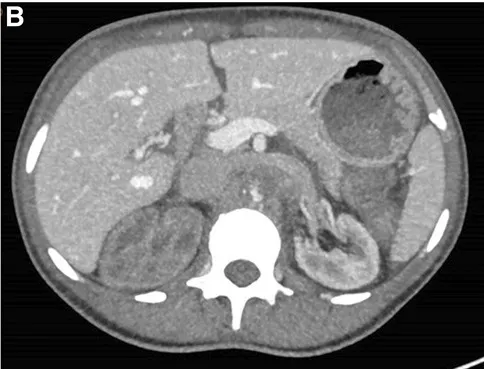

Realizado USG renal com Doppler que mostrou ecogenicidade e tamanho renal normais, mas sinais de oclusão aórtica na emergência da artéria mesentérica superior, o que foi confirmado por tomografia computadorizada com contraste (Figura 1).

A TC também revelou importante circulação colateral na parede abdominal, permitindo suprimento sanguíneo suficiente para os membros inferiores. Apenas o rim esquerdo mostrou captação residual de contraste (Figura 1), sugerindo rim direito isquêmico.

TC com contraste (reconstrução 3D) mostrando oclusão aguda da aorta justa-superior da artéria mesentérica. (A) Oclusão aórtica justa-superior à artéria mesentérica (marcada com um ⊗) juntamente com vasos colaterais na parede abdominal (B) Rim esquerdo com realce de contraste e rim direito sem realce sugerindo falta de perfusão renal.